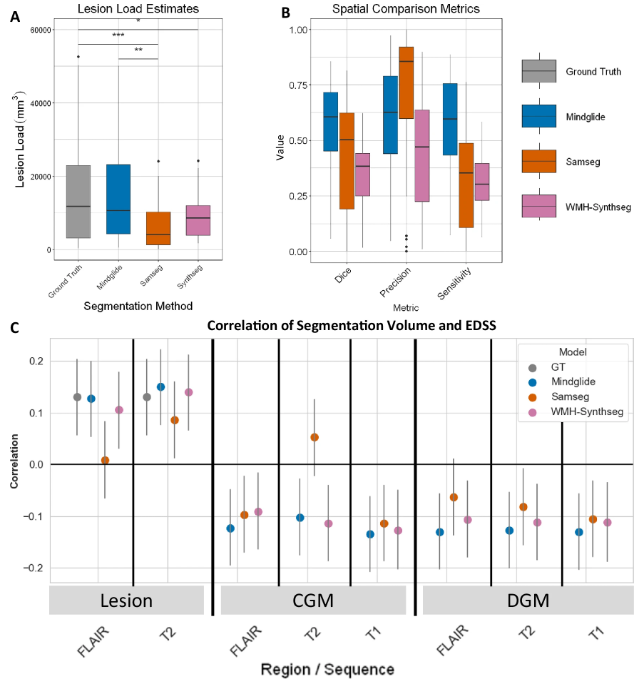

为了评估 MindGlide 的验证效果,研究人员将其与现有最先进的技术进行了对比,比对对象分别为 WMH-SynthSeg 和 SAMSEG,其中前者能够从不同分辨率和对比度的扫描中同时分割白质高信号和大脑解剖结构,后者能够在不同 MRI 对比度下稳健分割病变和大脑结构。

首先,实验比较了三者与人类专家标记病变分割与残疾的一致性情况,如下图所示。MindGlide 与人工标记的真实病变之间的一致程度更高,中位数 Dice 得分为 0.606,SAMSEG 为 0.504,WMH-Synthseg 为 0.385。

性能比较概况

另外,在 PPMS 数据集中,MindGlide 得出的病变负荷与扩展残疾状态量表 (Expanded Disability Status Scale,EDSS) 的数值相关性也比现有技术更高。

在此之后,研究人员继续在 PPMS 临床实验中比较了 MindGlide 与其他分割工具和真实病变的治疗效果。实验结果显示 MindGlide 与基础真值非常接近,相比之下, SAMSEG 高估了治疗效果,WHM-Synthseg 则低估了治疗效果,表明了 MindGlide 的病变体积估计精度更高。